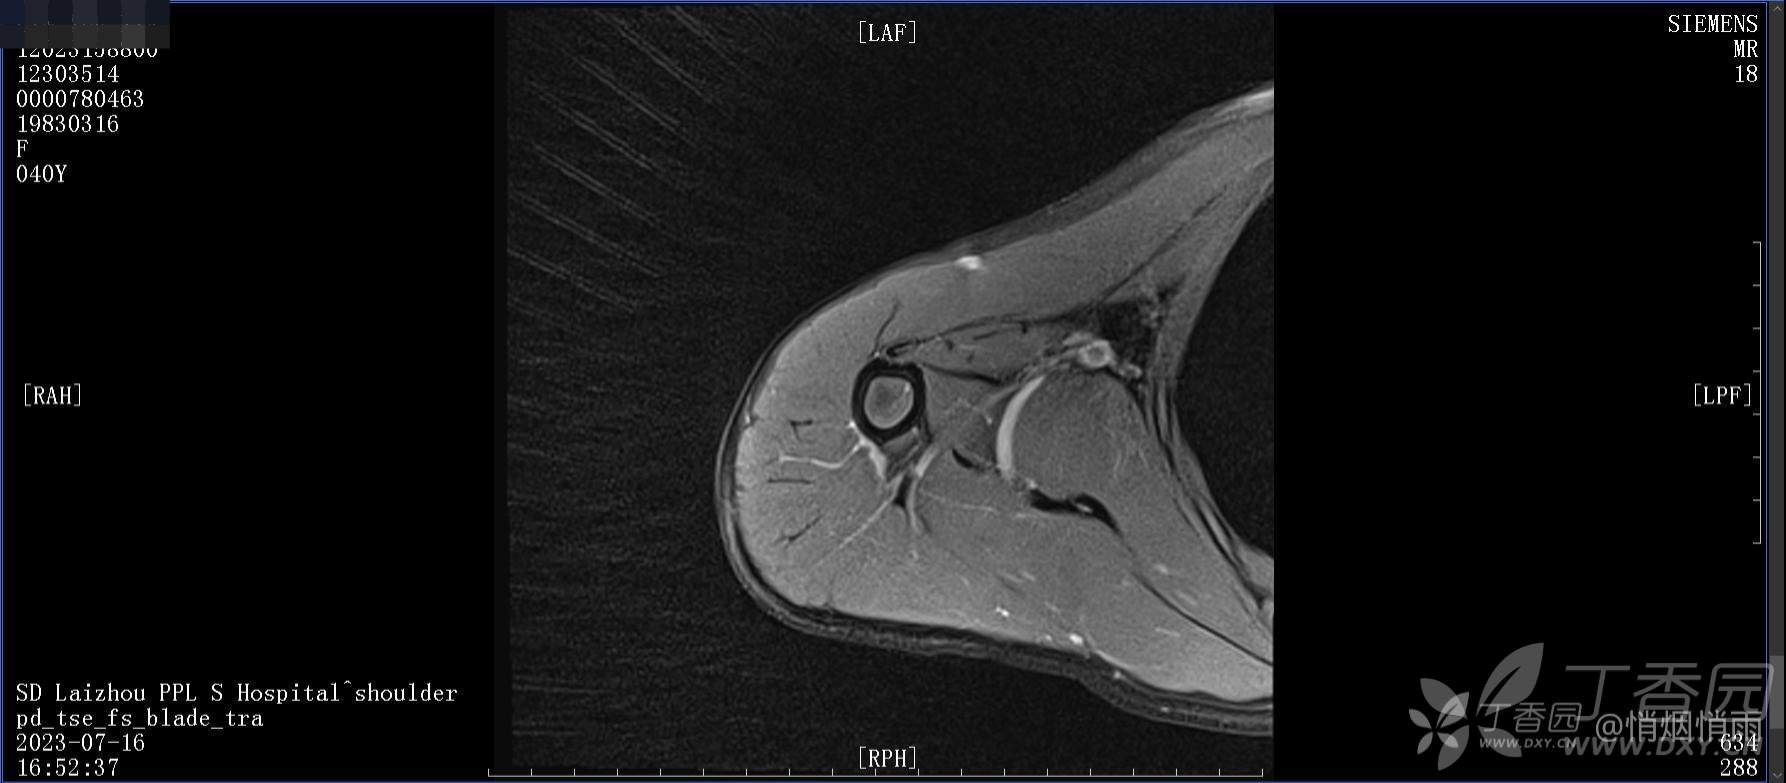

查体:右肩关节局部轻度肿胀,肩胛区压痛明显,痛处不固定,肩关节痛性活动受限,jobe test(+),lift -off test(+),中指、环指感觉较余指减退,余肢端感觉及血运情况可。

目前的诊断,暂时依据辅助检查诊为肩袖损伤,但是患者疼痛的性质和特点,却不是单纯的肩袖损伤所致。考虑过胸廓出口综合征,但是该疾病会出现肩胛区的疼痛吗?(由于考虑到费用的问题,没再进行下一步的检查)带状疱疹会有如此的症状吗?